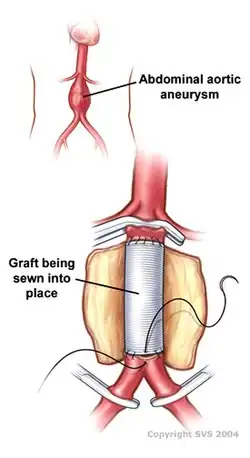

Open infrarenal aortic repair model | |

An abdominal aortic aneurysm (AAA) refers to aneurysmal dilation of the aorta confined to the abdominal cavity. Most commonly, aneurysms are asymptomatic and located in the infrarenal position. Often, they are discovered incidentally or on screening exams in patients with risk factors such as a history of smoking. Patients with aneurysms which have a diameter less than 5 cm are at <1% rupture risk per year. When the aneurysm meets size criteria it can be treated with aortic replacement or EVAR.

Abdominal aortic aneurysms can be classified as infrarenal, juxtarenal, pararenal or suprarenal as depicted in the illustration.

Abdominal aortic aneurysms can be classified as infrarenal, juxtarenal, pararenal or suprarenal as depicted in the illustration. -